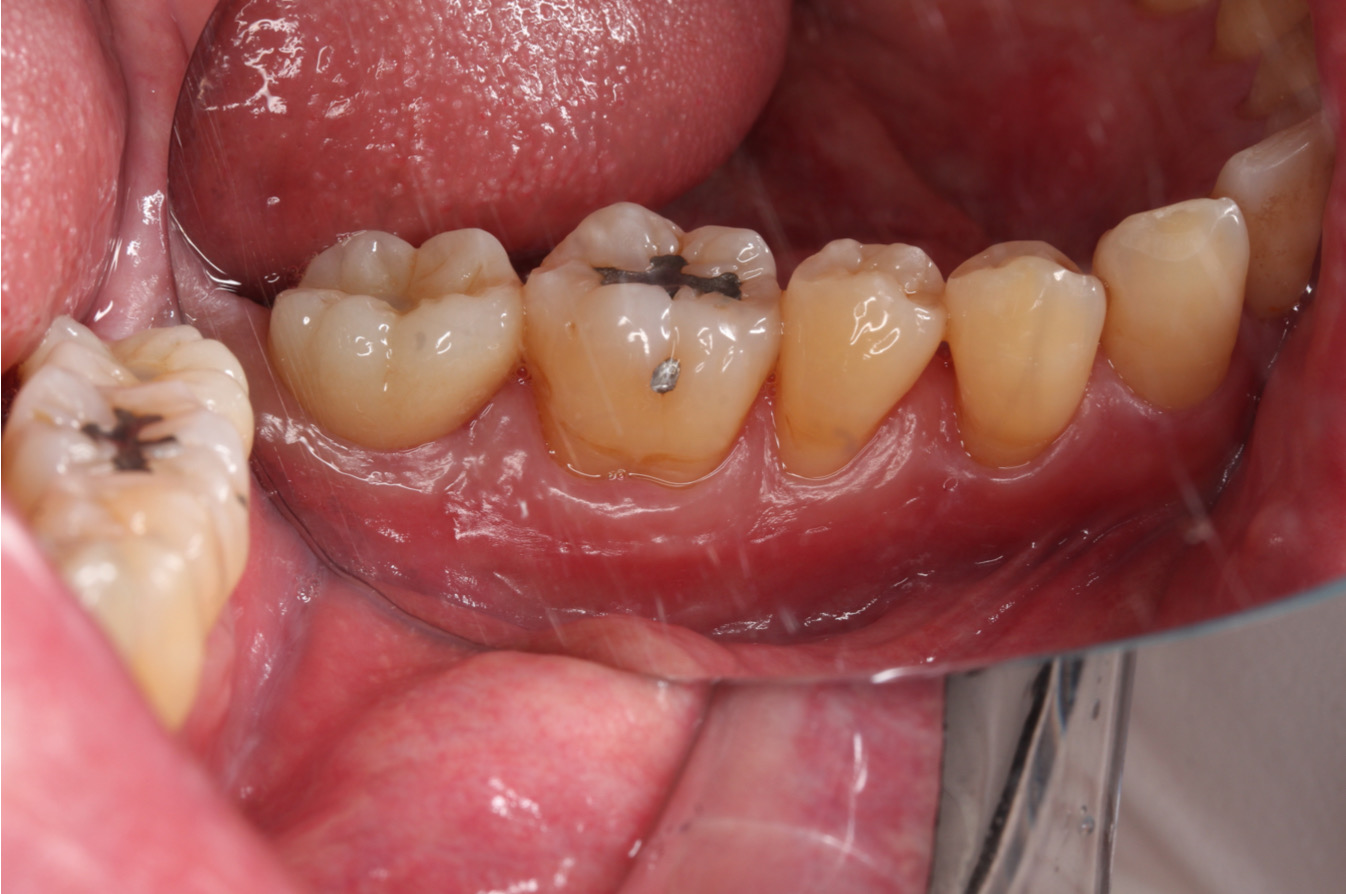

【治療醫師:林農翔 醫師】 即拔即種 即拔即種是一種結合了拔除受損或斷裂的牙齒以及立即植入人工牙根的步驟,並在同一天內完成整個手術過程。 步驟通常是牙醫先進行局 …